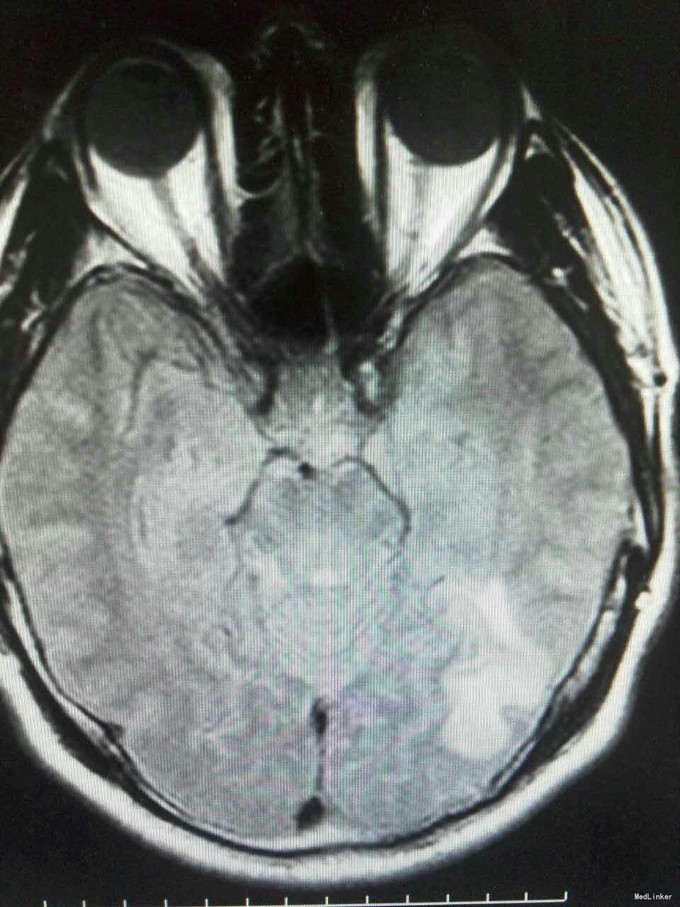

患者姜磊,男,49岁,主因"发作性视野缺损、失认8年余"于2015-11-20再次入我院,患者缘于8年前无诱因出现发作性视野缺损,伴阅读能力、理解力、认知能力下降,每次发作症状持续约3-5分钟左右,可自行缓解,无意识丧失、视物旋转、言语不利,无肢体活动障碍、大小便失禁。入院复查头颅MRI平扫+增强示:原左侧小脑幕、颞叶炎症治疗后,与2014-09-10日片比,病灶较前增多、增大。8年来间断在我院以:颅内非特异性炎症、症状性癫痫、高血压病 住院治疗,患者症状时轻时重,病灶反反复复,激素治疗有效。 病史汇报: 于2007年12月12日因"发作性视野缺损、失认1月"入我院,查头颅MRI示:左侧幕上颞底片状异常信号,并局部强化,考虑:炎症可能,肿瘤不排除;行腰穿检查,颅压120mmH2O ,外观清亮,脑脊液常规、生化均正常。脑电图轻度异常。给予复方磺胺甲恶唑片、青霉素、阿昔洛韦、激素(醋酸泼尼松片)等治疗。 2008年1月8日复查头颅MRI示:原左侧幕上颞底炎性病变范围缩小,综合考虑原颅内病变为炎性病变。于2008年1月19日出院,共住院37天。出院后仍间断出现发作性视野缺损症状。于2008-5-6复查头颅MRI示原左颞叶病变范围有缩小,支持局灶性脑炎的诊断。于2008.5.22~6.12予青霉素480万单位2/日巩固治疗30天。鉴于反复出现发作性视野缺损症状,于2008.6.5诊断性服用卡马西平片后上述症状未再发作,于是坚持服用卡马西平片(0.1g3/日)1年,服药期间未再出现发作性视野缺损症状。 于2012-05-29再次因"发作性双眼右侧视野缺失、闪烁感6天"入院,查头颅MRI示:原左侧幕上颞叶病变治疗后改变,考虑为炎性病变,结核可能。行腰穿示压力125mmH2O,脑脊液常规:颜色:无色,透明度:水样透明,潘氏试验:阴性,红细胞计数:80×106/L,白细胞计数:0x106/L,单个核细胞75%,多核细胞20%,脑脊液生化:蛋白508mg/L,葡萄糖3.3mmol/L,氯化物115.4mmol/L。脑电图印象:基本节律为低-中幅的α波, 频率调幅调节欠佳,分布可,左侧枕区波幅可见较右侧枕区减低。头前区可见少量低幅θ波及β波。深呼吸中见4-5hz慢波增多,有时呈短至中程节律,头前区为著,左侧偏胜。深呼吸后恢复好。睁闭眼试验:半抑制。闪光刺激:未见异常。脑电地形图:以α功率为主,可见θ功率。结论:轻度弥慢性异常脑电图及地形图;给予改善循环、营养神经、活血化瘀、脱水、激素等对症治疗。住院期间未再出现上述发作。 于2013-1-5再次因"发作性双眼右侧视野缺失、闪烁感1周。"入院,行头颅MRI示:左侧颞叶病变治疗后改变,与2012-07-24日片比,左侧小脑幕病变较前增大,左侧颞叶出现新病灶。给予改善循环、营养神经、活血化瘀、抗癫痫、抗感染(青霉素)、激素冲击(甲强龙)治疗后病情好转,于2013-4-15复查头颅MRI病灶再次缩小。患者出院后上述症状仍偶有发作。 于2014-5-12、2014-9-10复查头颅MRI病灶有增大趋势,再次给予抗炎(激素)等对症治疗后,于2014-11-24再次复查头颅MRI示:原左侧小脑幕、颞叶病变治疗后改变,与2014-09-10日片比较,较前明显缩小,水肿较前明显减轻。